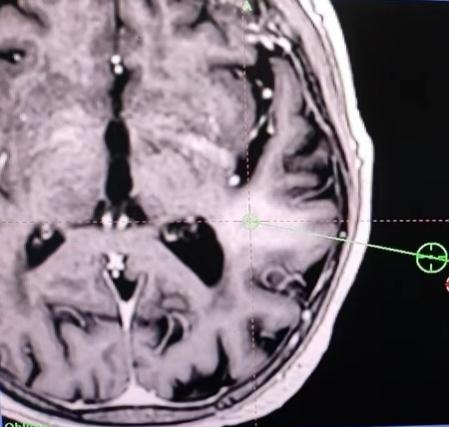

70多岁的陈老太太今年1月份出现行走不稳合并言语迟钝,就诊于我院绩溪路院区。综合多种检查结果及多科室会诊讨论意见,考虑临床诊断为B细胞淋巴瘤,华氏巨球蛋白血症的特殊表现Bing-Neel综合征可能。华氏巨球蛋白血症是淋巴瘤的一种类型,也是2023年国家公布的第二批罕见病之一,而Bing-Neel综合征又是该病尤为罕见特殊的一种临床综合征,表现为头痛眩晕、共济失调等中枢神经系统症状。患者经血液内科刘沁华医师治疗组诊治,症状逐步改善。然而,今年7月以来,患者症状再次加重,影像学检查提示颅内小脑,基底节区及颞叶多发占位。由于患者高龄,且颅内占位定性诊断困难,患者下一步的治疗方向成为困难。

经医务处协调,组织多院区MDT会诊,南区神经外科王毅副主任医师表示,可在影像引导下行脑组织活检。脑组织活检术是一种仅需颅骨钻孔,使用直径2mm左右的活检针获取病变标本的微创手术。通过脑活检术可以明确颅内占位性质;若是淋巴瘤,还可以通过病理明确免疫分型,从而指导下一步的精准治疗。